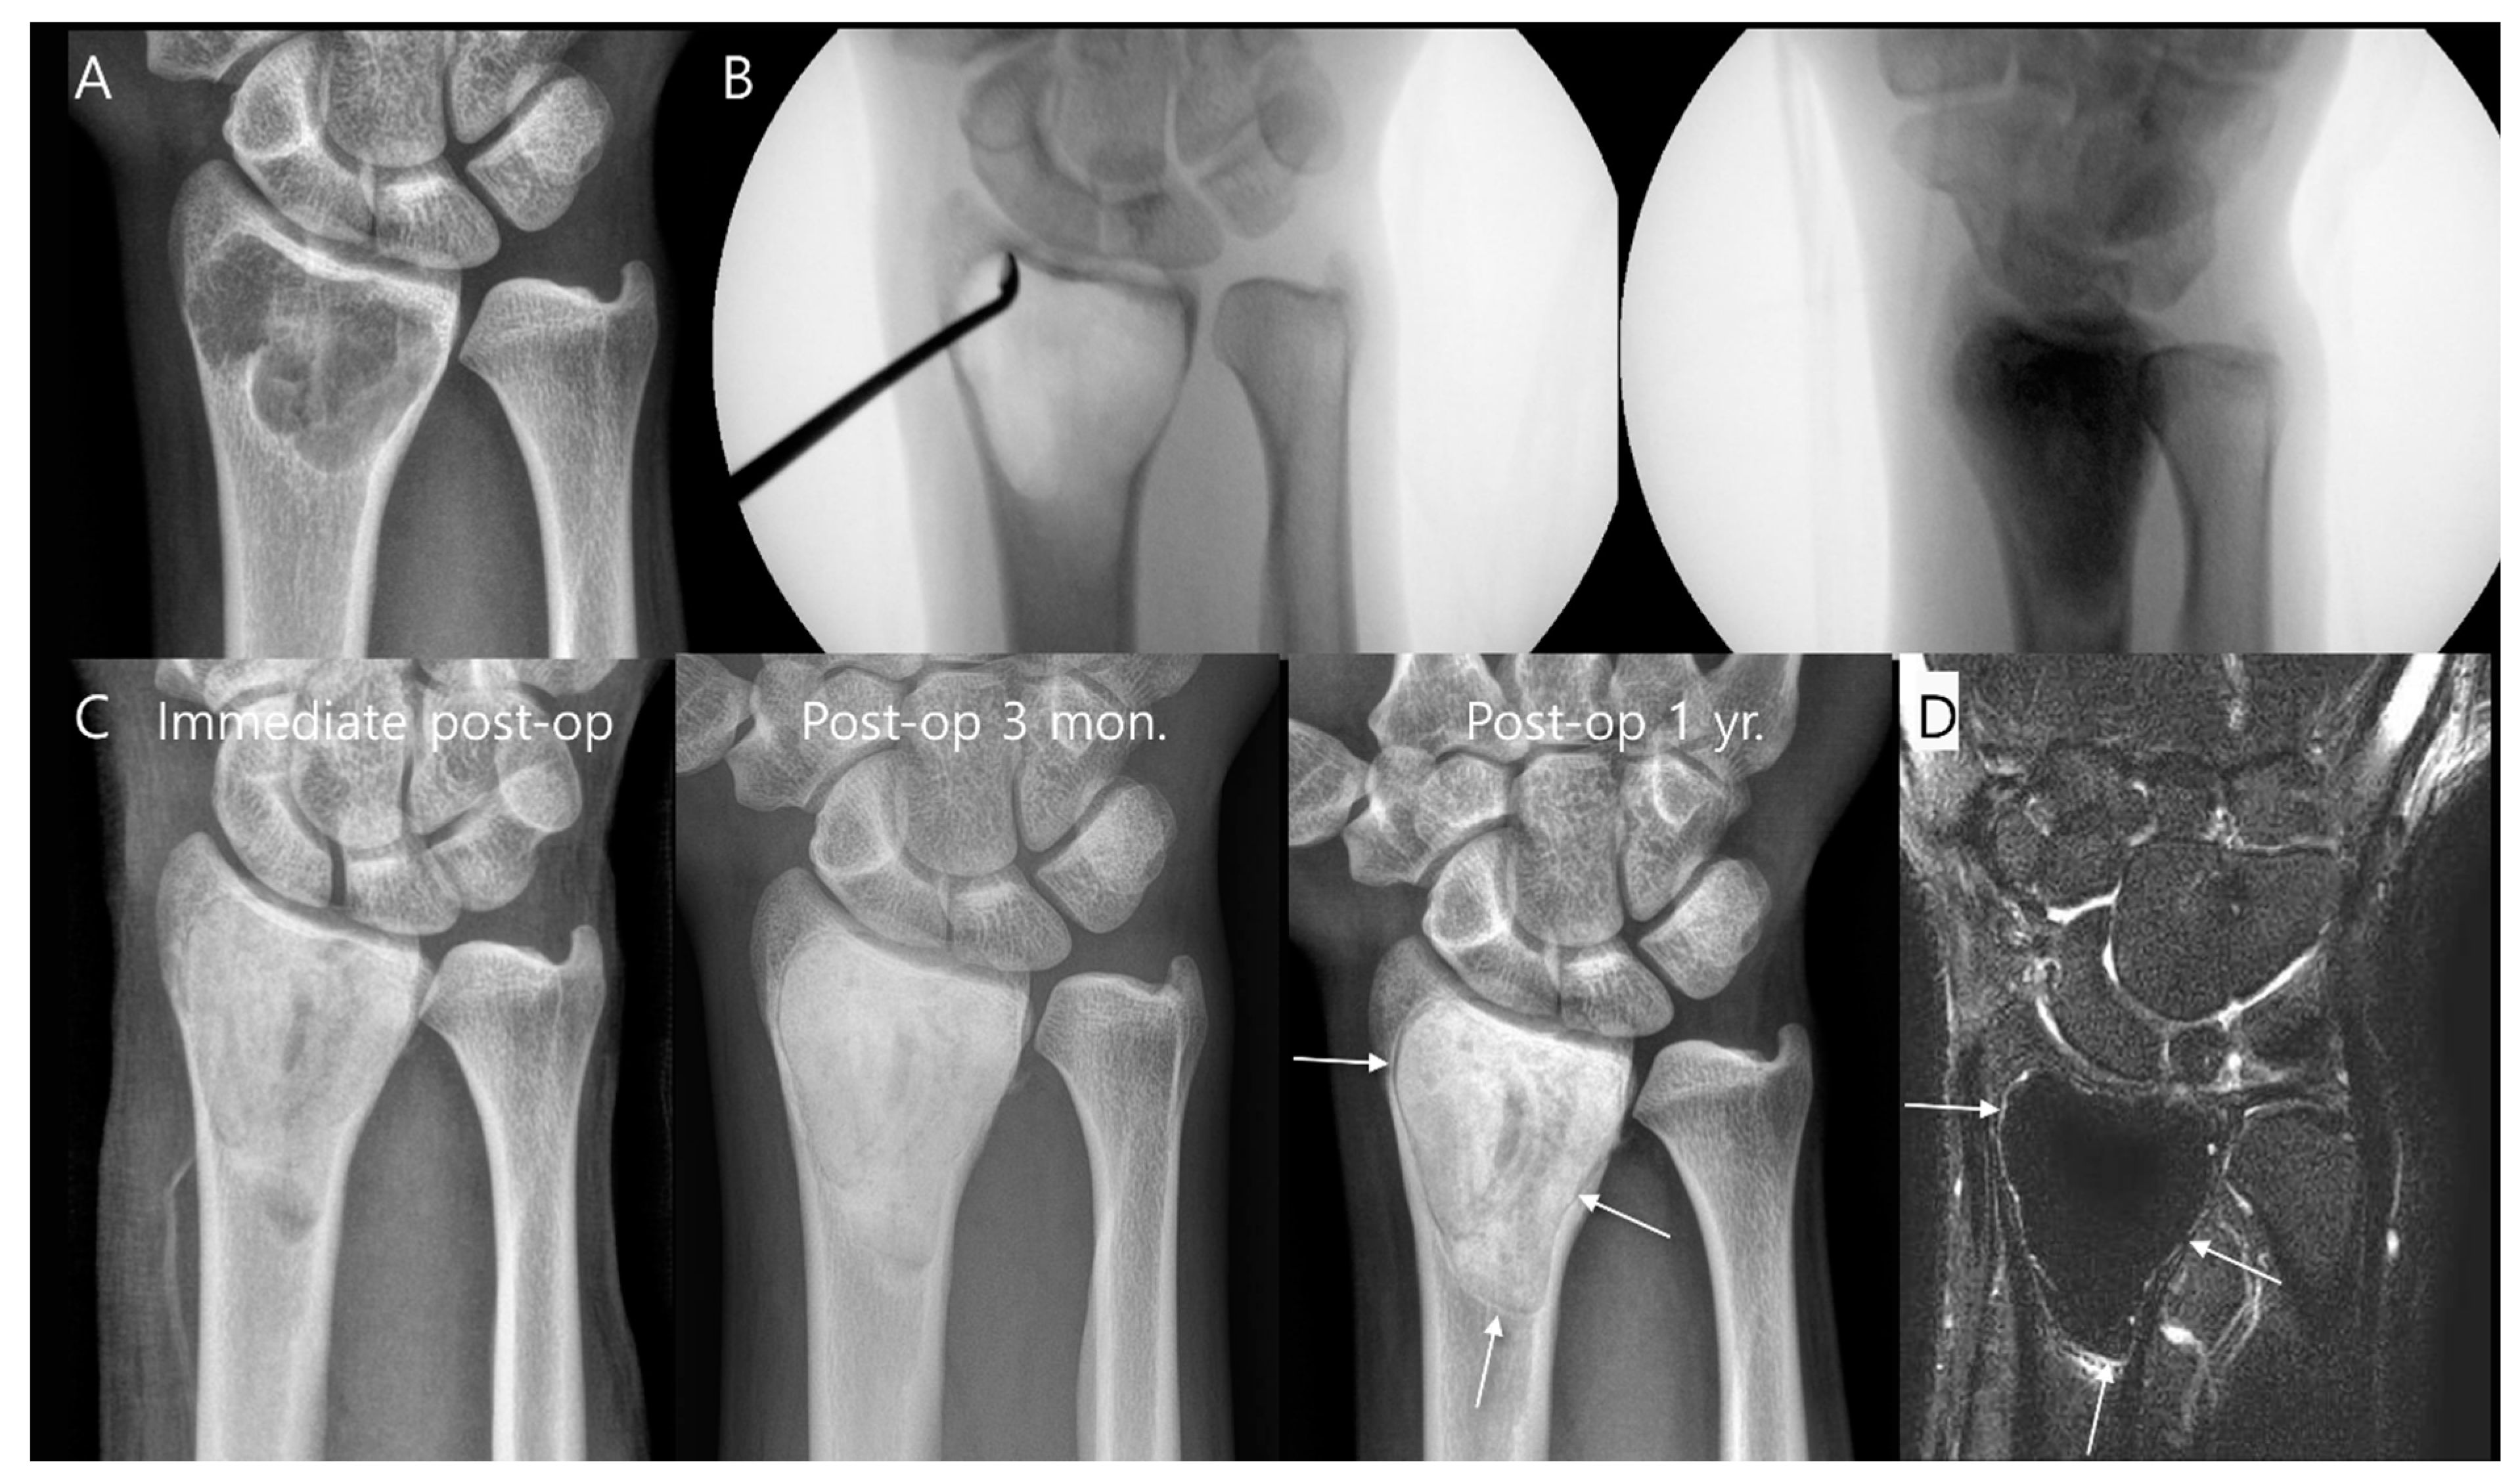

3.1. Bone Tumors

- Turcotte, R.E.; Stavropoulos, N.A.; Toreson, J.; Alsultan, M. Radiographic assessment of distal femur cemented stems in tumor endoprostheses. Eur. J. Orthop. Surg. Traumatol. 2017, 27, 821–827. [Google Scholar] [CrossRef]

- Henderson, E.R.; Groundland, J.S.; Pala, E.; Dennis, J.A.; Wooten, R.; Cheong, D.; Windhager, R.; Kotz, R.I.; Mercuri, M.; Funovics, P.T.; et al. Failure mode classification for tumor endoprostheses: Retrospective review of five institutions and a literature review. J. Bone Jt. Surg. 2011, 93, 418–429. [Google Scholar] [CrossRef]

- Shah, A.; Cardoso, F.N.; Souza, F.; Montreuil, J.; Pretell-Mazzini, J.; Temple, H.T.; Hornicek, F.; Crawford, B.; Subhawong, T.K. Failure Modes in Orthopedic Oncologic Reconstructive Surgery: A Review of Imaging Findings and Failure Rates. Curr. Oncol. 2024, 31, 6245–6266. [Google Scholar] [CrossRef]